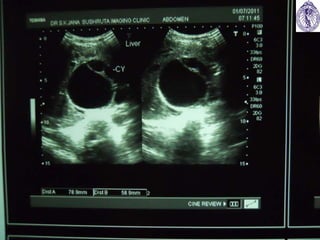

 IMAGING: USG is Inv of choice (Gharbi US classification of

1981 & WHO-IWGE 2003 classification)

CASE HISTORY  An26 yrs old female presented with dull pain right side of upper abdomen, a dragging sensation over right hypochondrium and occasional fever nearly one month • Pain not relieved with analgesics • Examination revealed mild hepatomegaly • Routine blood test was normal • Advised for imaging study of abdomen